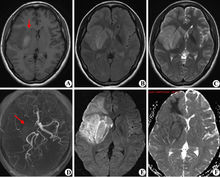

腦梗後遺症腦梗發病一年後仍有肢體、語言障礙等症狀就屬於後遺症了,醫學上稱之為腦梗的後遺症期。30%的腦梗患者會留下不同程度的後遺症,在我國30%-40%的腦梗患者面臨復發。腦梗患者之所以會出現偏癱、語言障礙等後遺症,是由於腦組織內部出現血粘度高、血脂高、血壓高、血小板聚集等血液病變,和動脈粥樣硬化斑塊形成或管腔狹窄等血管病變,由於這兩種病變共同作用的結果。導致腦局部的血流中斷和腦組織缺血缺氧甚至壞死,如果影響到由腦神經控制的運動中樞神經系統,就會出現偏癱等相應的後遺症(從人的大腦半球分工來講,右側大腦半球通過運動中樞管理著左側肢體運動;左側大腦半球,通過運動神經管理著右側肢體運動。任何一側發生病變,都會導致對側偏癱)。如果影響到腦神經控制的語言中樞神經,就會導致語言障礙甚至失語等相應神經系統症狀和體徵。要想有效改善腦梗後遺症偏癱、語言不利等後遺症的發生、降低病症復發威脅,患者在合理飲食調節和功能康復主動與被動訓練的同時,通過可靠的藥物治療,即通過血液及血管病變同時入手,改善受損腦細胞,保護未損腦細胞,創造一個良好的腦內環境,防止血栓再次形成,動脈粥樣硬化斑塊再次堵塞血管的治療手段,應是腦梗後遺症患者康復的關鍵。